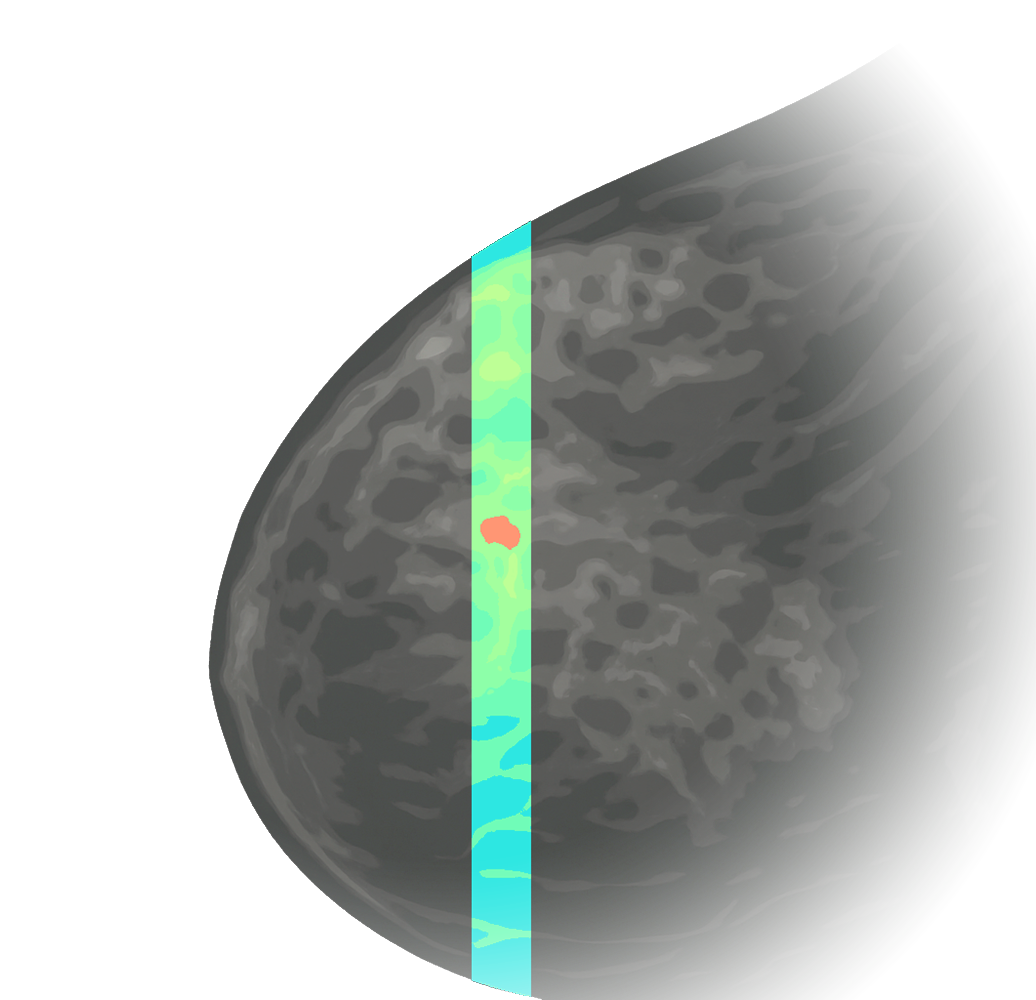

At Calidar, we are building next-generation X-ray diffraction imaging to reveal molecular-level signatures of disease. Our patented 4D Mammography technology measures these signatures from the breast noninvasively, providing a new dimension of data with the goal of earlier, more accurate diagnosis of breast cancer.

4D Mammography

Maps X-ray scatter fingerprints linked to cancer.

Light-based 4D Mammography concept illustration